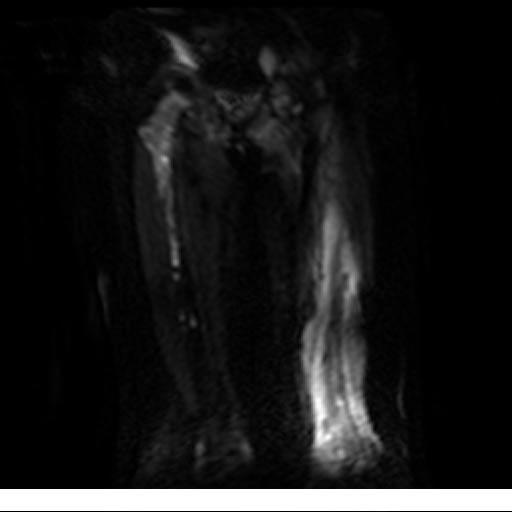

Se realiza estudio de MRI de muslo izquierdo en diferentes planos, con secuencias de Spin Echo, GRE; ponderadas a T1 y a T2, se utilizan pulsos de saturación de grasa y se administra medio de contraste IV a base de Gadolinio en base al peso del paciente.

La diáfisis femoral izquierda muestra reacción perióstica importante, se extiende desde el cuello del fémur, invade trocánteres, diáfisis femoral, medial y distal, es compatible con un proceso infeccioso óseo, el complejo muscular del muslo se ve edematizado.

Hallazgos en Resonancia Magnética (RM)

La resonancia es la modalidad de elección para valorar la extensión intramedular y la infiltración en tejidos blandos, brindando una imagen más detallada del compromiso tumoral. Los hallazgos característicos incluyen:

Lesión de señal heterogénea en secuencias T1 (hipointensa) y T2/STIR (hiperintensa), que refleja necrosis, hemorragia y contenido celular diverso.

Realce intenso y heterogéneo tras la administración de contraste (gadolino), lo que indica vascularización tumoral.

Compromiso de la médula ósea adyacente y de estructuras vecinas, como músculos y neurovasculatura.

Posible presencia de edema óseo y necrosis central.